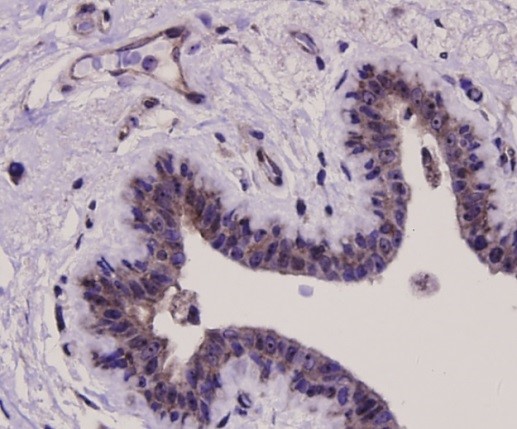

Fig3:

Immunohistochemical analysis of

paraffin-embedded human gallbladder tissue

using BAX antibody. Counter stained with

hematoxylin.